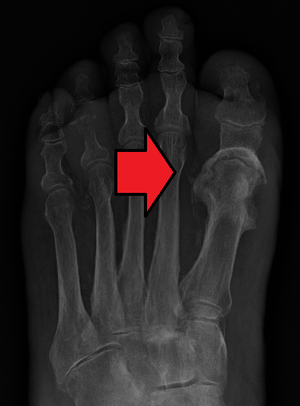

| Osteomyelitis of the 1st toe | |

Radiographs and CT are the initial method of diagnosis, but are not sensitive and only moderately specific for the diagnosis. They can show the cortical destruction of advanced osteomyelitis, but can miss nascent or indolent diagnoses.[12]

Diagnosis of osteomyelitis is often based on radiologic results showing a lytic center with a ring of sclerosis.[1] Culture of material taken from a bone biopsy is needed to identify the specific pathogen;[15] alternative sampling methods such as needle puncture or surface swabs are easier to perform, but do not produce reliable results.[16][17]